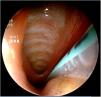

Recién nacido a término con rasgos dismórficos, ventriculomegalia bilateral y comunicación interventricular e interauricular que precisa ingreso por distrés respiratorio que requiere soporte respiratorio con ventilación mandatoria intermitente a 30rpm. Presenta episodios de tos y atragantamiento en todas las tomas. Ante la sospecha de fístula traqueoesofágica, se indica una exploración de la vía aérea mediante lente rígida de 3mm en respiración espontánea. Se observa hendidura laringotraqueoesofágica tipo III (figs. 1 y 2). Se realiza laringotraqueoplastia por abordaje abierto. En el control endoscópico a los 16 meses se observa una hendidura grado 1 que precisa de nueva cirugía. En el último control, no se observan hendiduras, con normoposición de epiglotis y aritenoides unidos por la comisura posterior (fig. 3).

La hendidura laringotraqueoesofágica se caracteriza por un defecto en la pared posterior de la laringe que puede extenderse hasta la tráquea1. Puede asociar alteraciones cardíacas, urogenitales y craneofaciales1–3. En función de su extensión, existen cuatro subtipos. Las hendiduras laringotraqueoesofágicas tipo I pueden ser manejadas de manera conservadora. Se ha descrito la corrección endoscópica del grado I y II3. Los grados III y IV precisan de cirugía abierta por la extensión del defecto1–3. El diagnóstico requiere una alta sospecha en un neonato con dificultad respiratoria, tos y atragantamiento durante las tomas. La exploración de la vía aérea permite un diagnóstico certero. Además, es útil en el seguimiento para demostrar otras alteraciones como la laringomalacia y la traqueomalacia, así como estenosis subglótica o fístulas traqueoesofágicas.